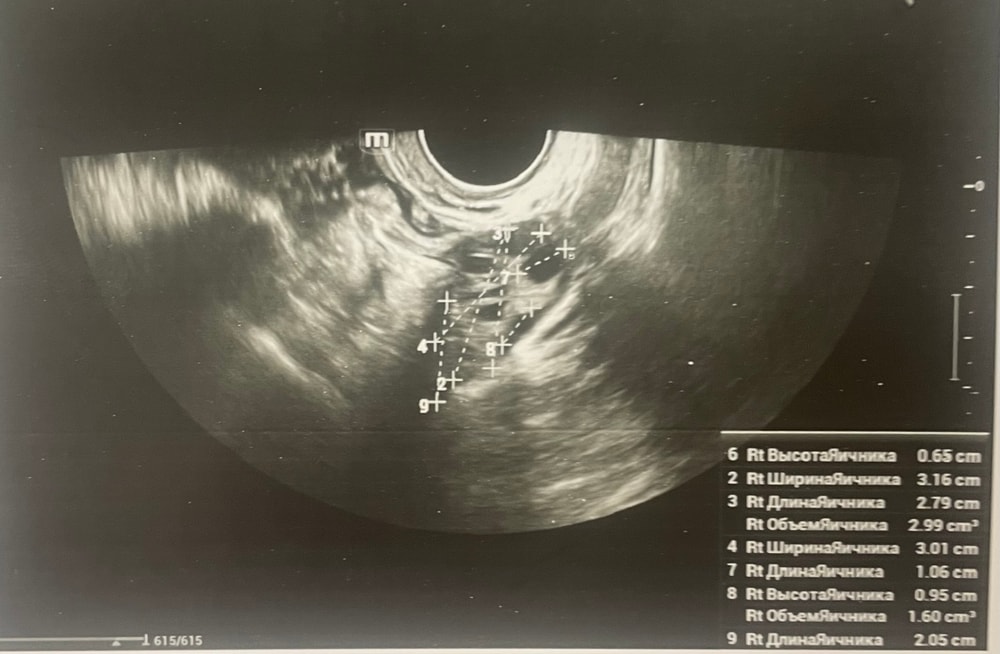

УЗИДобрый день, мы с мужем планируем беременность и в этом месяце произошло что то странное… дата начала последней менструации 4 октября закончилась 8, овуляцию отслеживала всю неделю почти сначала были бледные еле заметные полоски, 23 октября жирные четкие полоски, 24 октября стала чуть бледнее но яркая, вообщем положительный ещё был, с 25 числа тест уже отрицательный, через день после овуляции 26 числа стала странно себя чувствовать и во время овуляции болел живот то справа то с лева и поясница, так через день после начали болеть соски грудь вообще не болела, живот то болит то нет и с поясницей также, позже появилась небольшая изжога, нога немеет правая не знаю с чем связано), все это началось за 2 недели до месячных в середине цикла скажем так 29 числа пошла на узи спустя 6 дней грубо говоря гиня сказала что у меня была очень хорошая овуляция, что её признаки сохраняются до сих пор так скажем, желтое тело СПРАВО 20 мм, мои симптомы и все это очень похоже на беременность сказали большая вероятность, я очень была рада и надеялась, после узи появились выделения с комочками, до этого были просто густые белые выделения, утром тоже самое, пошла опять к гинекологу она сказала это может быть при ранец беременности сказала какие свечи купить, вечером я попала в не большое ДТП, удар был в поясницу и копчик, живот начал тянуть и поясница сильно болеть, начала болеть сама грудь помимо сосков, живот прошел относительно быстро, а вот поясница ломит до сих пор, решила сходить ещё раз на узи очень испугалась, на узи я пошла 31 через два дня после предыдущего и уже к другому гинекологу, моя на больничном, она сказала, что у меня отсутствуют даже косвенные признаки беременности и желтое тело с ЛЕВО А НЕ С ПРАВО, я не понимаю как такое может быть, очень расстроилась и совсем забыла про фото узи, она мне его не дала только заключение и как выяснилось уже не дадут оно не сохранилось, сказали переделывать, я очень доверяю своему гинекологу, но по заключению второго врача о беременности не может быть и речи в этом цикле, я не понимаю как желтое тело оказалось с лево если оно точно было справа в этом я уверена, а вторая врач уверяет во Братном, живот в обуляцию хоть и болел с двух сторон но больше справа помойму, вообщем я не понимаю есть ли шанс что я беременна или все таки нет, я понимаю что это слишком рано, до задержки ещё 4 дня, но мне плохо уже неделю по симптомам даже больше это же не просто так, я прикреплю фото заключения, могу ли я быть беременна, если посмотреть на эти заключения хотябы, подскажите пожалуйста фото узи относятся к 29.10, без фото 31.10